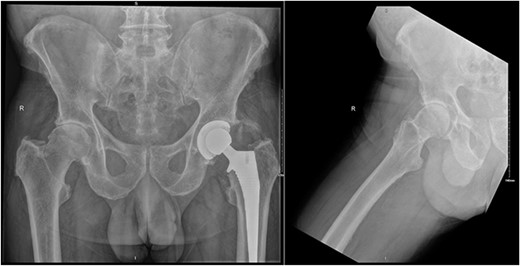

Our patient is a 74-year-old male who underwent primary total hip replacement for right hip pain. This was performed using a collared, fully hydroxyapatite-coated, uncemented stem, as well as an uncemented acetabular component with a ceramic-in-polyethylene bearing surface (Corail-Pinnacle, Depuy-Synthes, IN, USA). His recovery was uneventful until 6 weeks postoperatively when he presented to his routine outpatient appointment with significant erythema, swelling, and tenderness over his right hip wound. This was associated with difficulty weightbearing on the operative side due to discomfort. His background medical history included polymyalgia rheumatica for which he took Methotrexate 7.5 mg weekly, Folic acid 5 mg weekly, Celecoxib 200 mg BD, and pre-diabetes which was diet controlled. His other medical history included prostate cancer in remission since 2012, renal calculi, dyslipidaemia, and hypertension. He had a contralateral total hip replacement performed in 2020 (Fig. 1). He had no known drug allergies. At baseline, he was independently mobile. He was a non-smoker and non-drinker.

Preoperative AP pelvis and lateral right hip radiographs of our patient showing right hip osteoarthritis and previous left THR in situ.